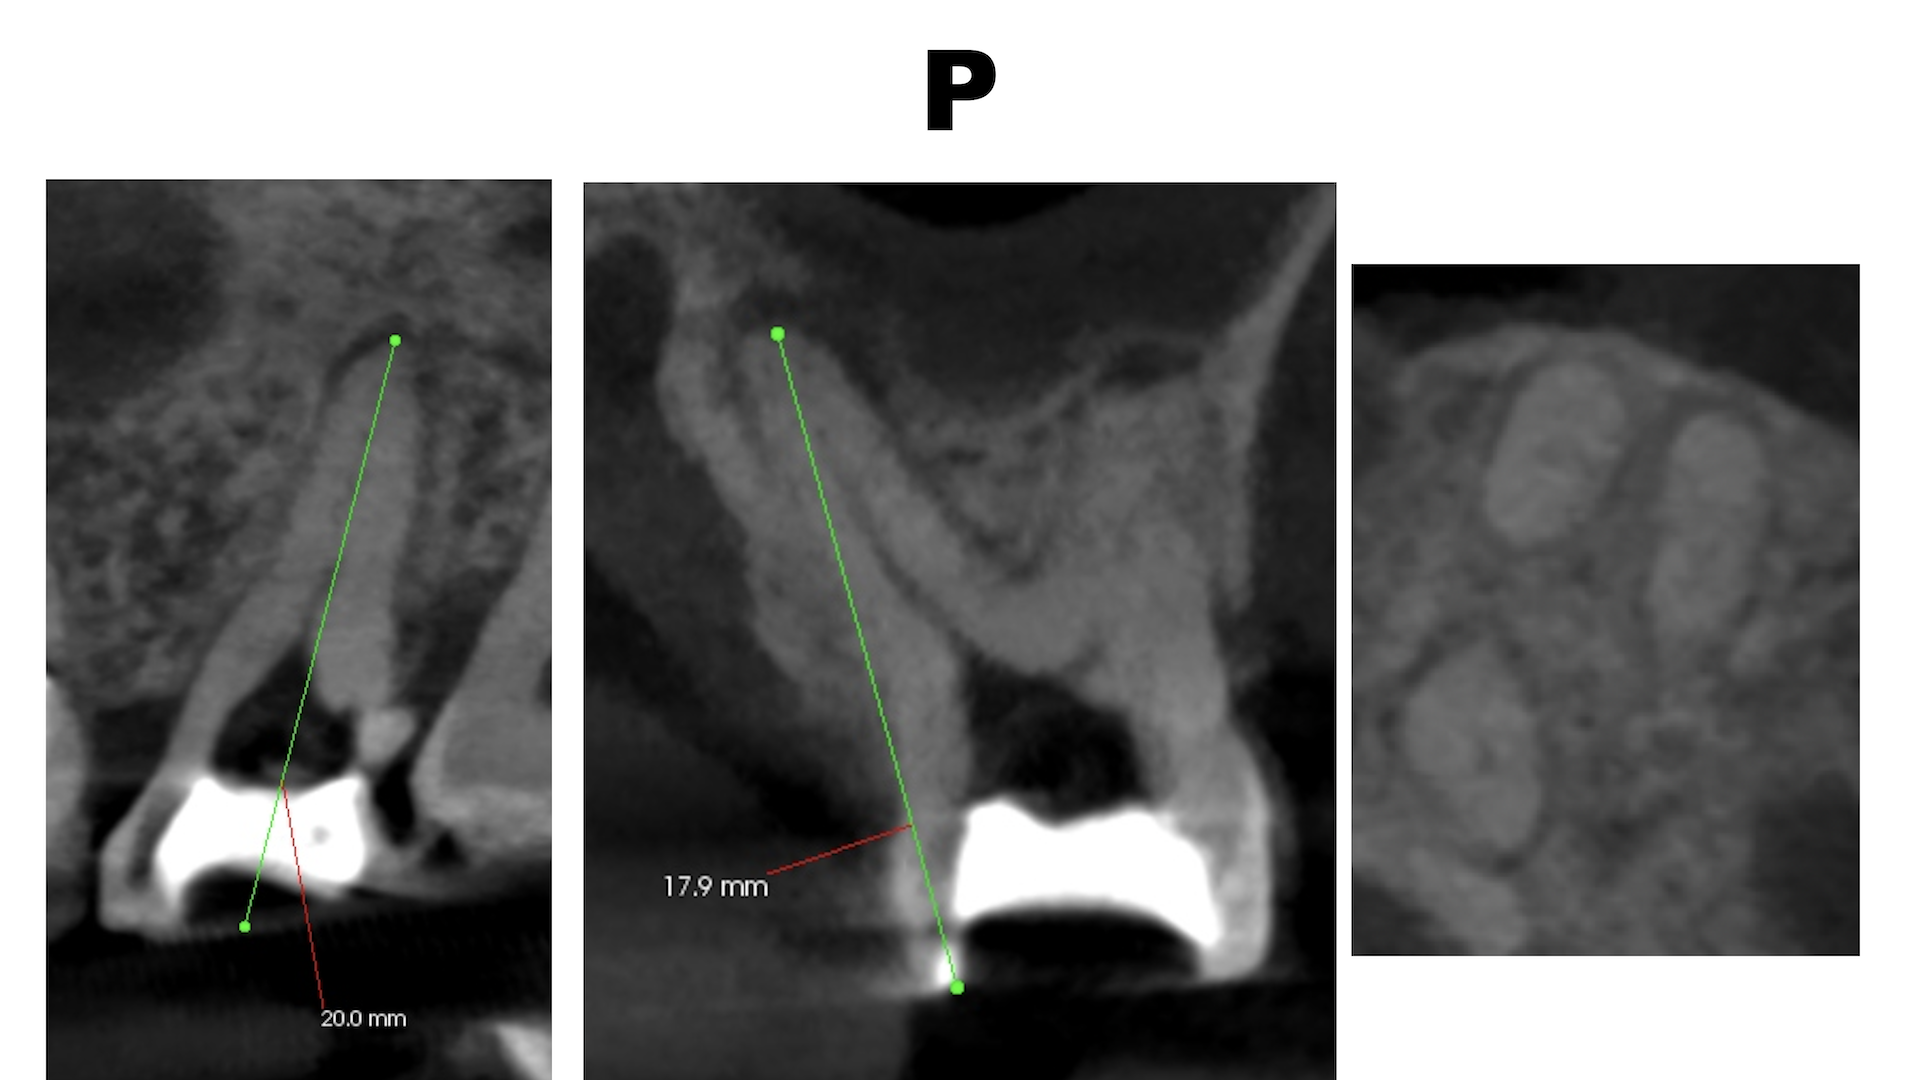

#14

MB

MB2

DB

P

B

その際は、

MB1

#13

おおよその作業長が類推できる。